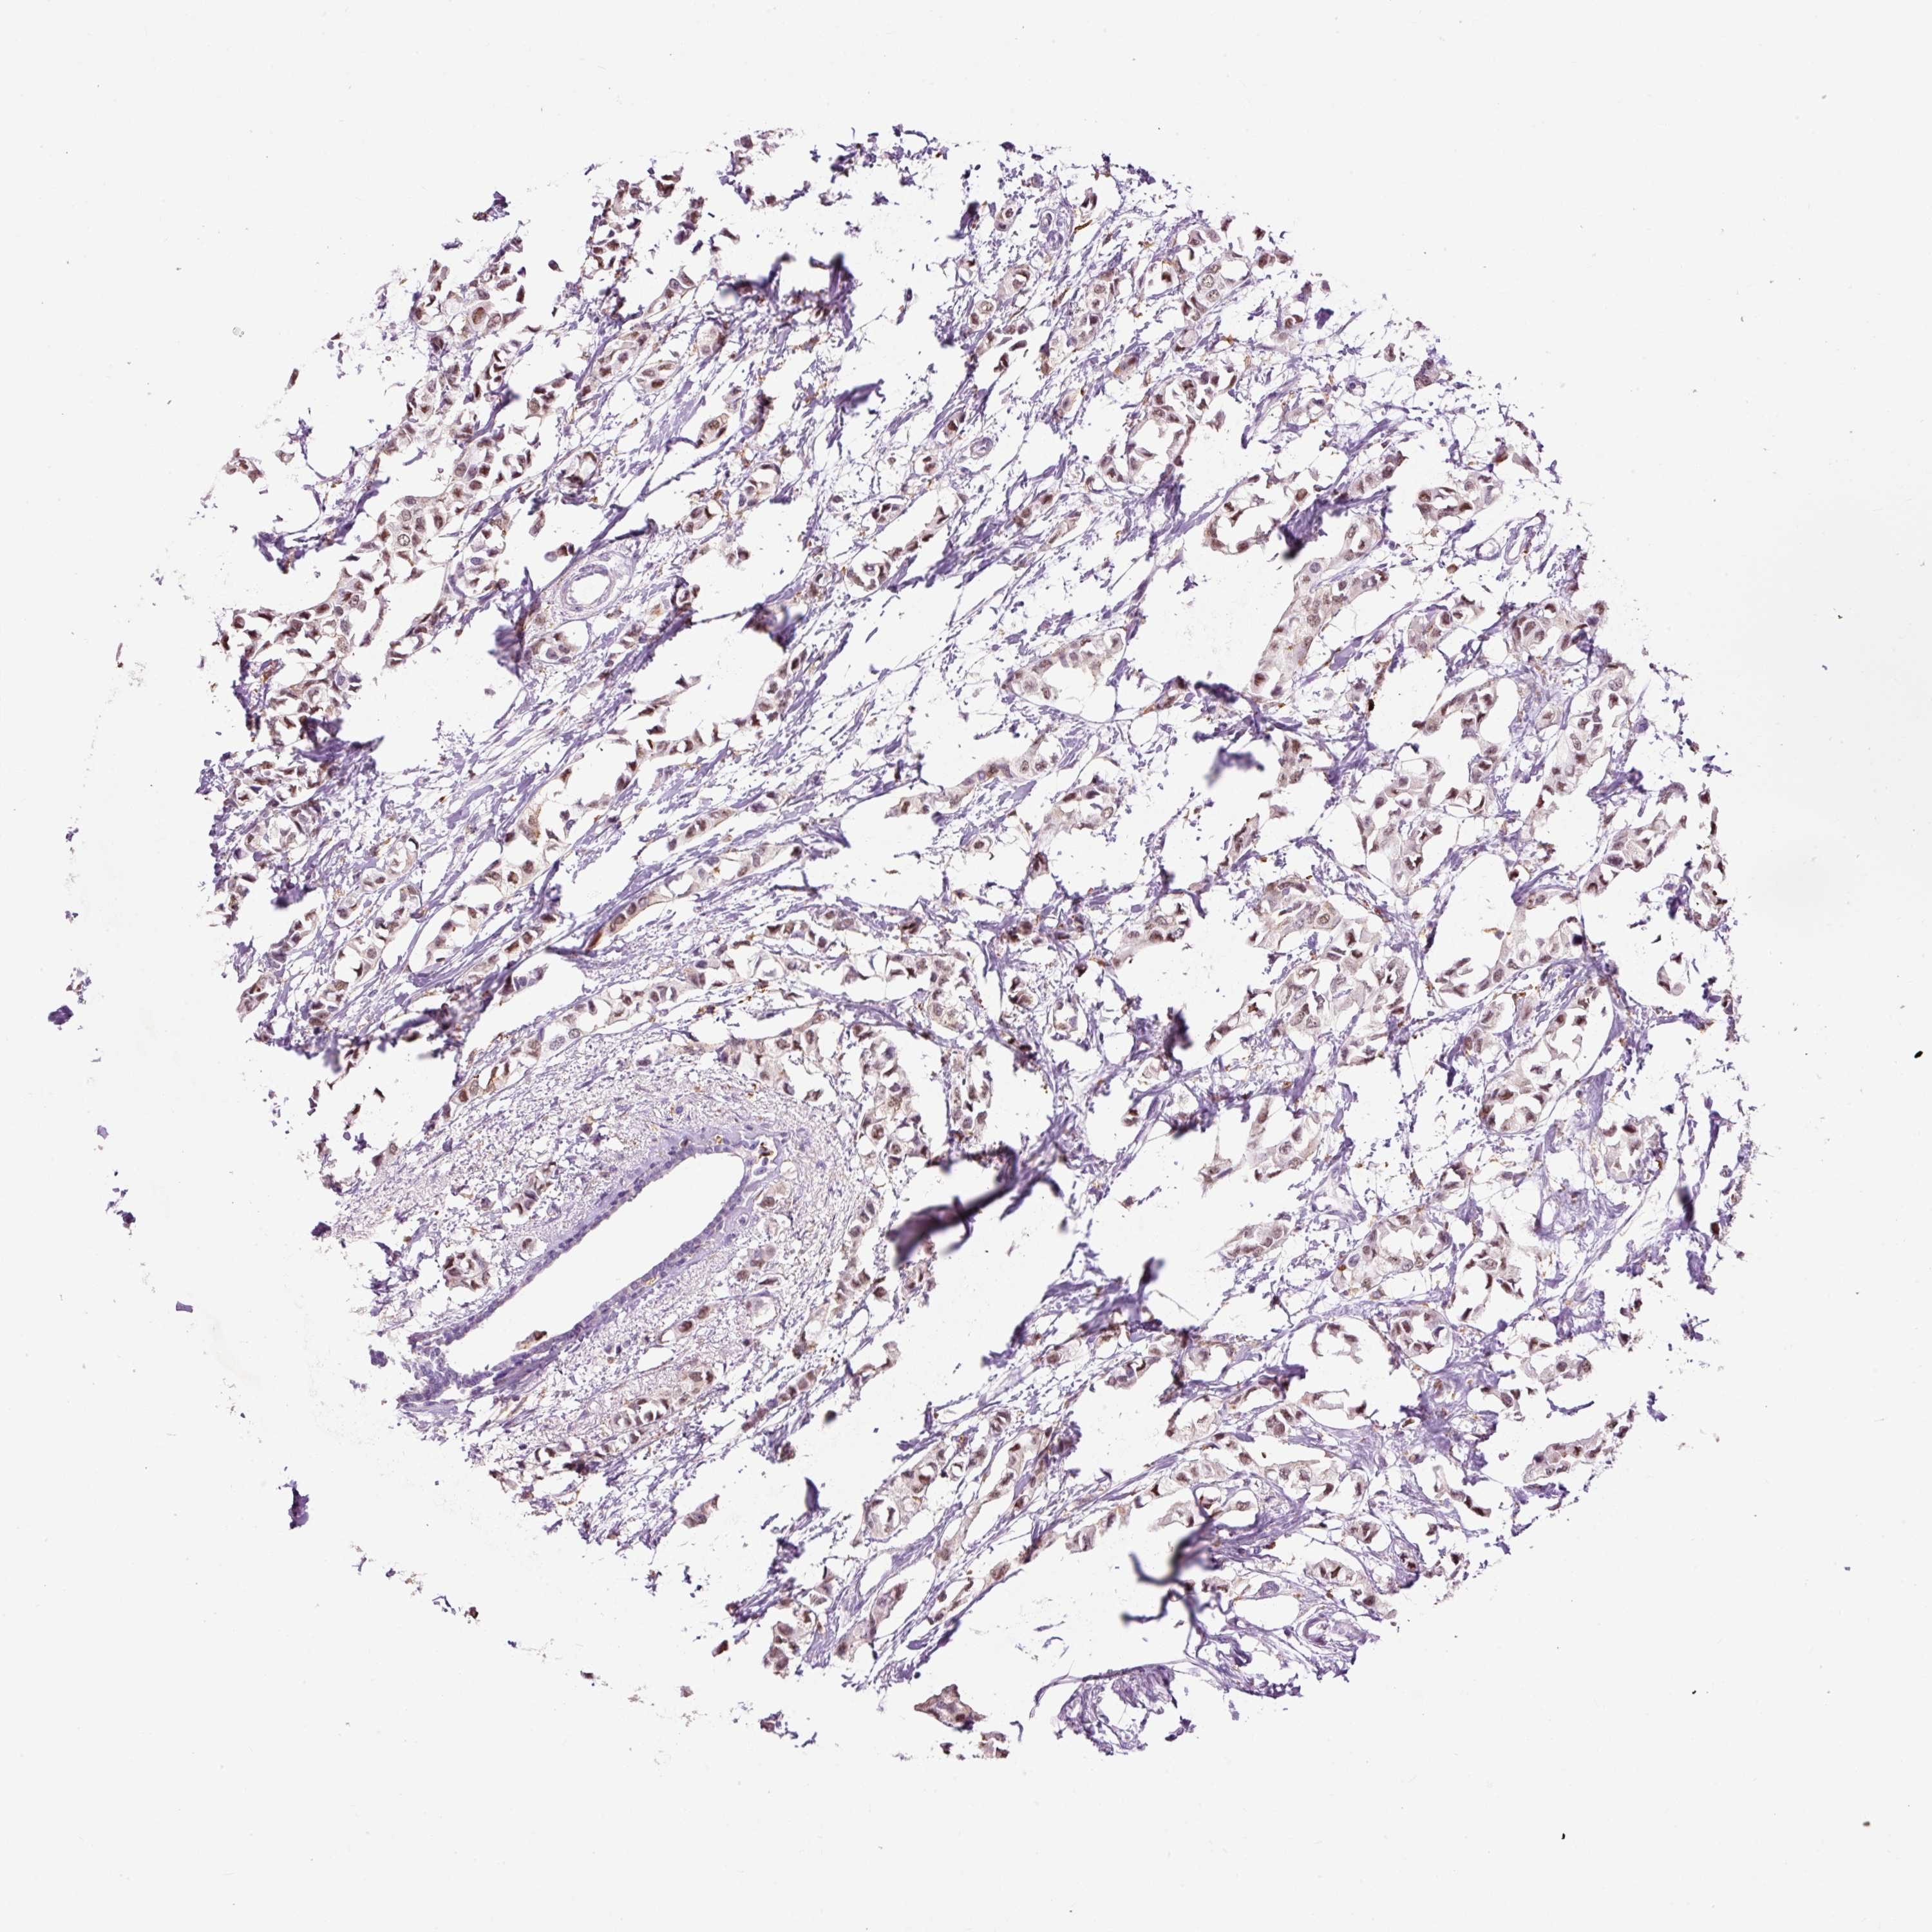

CANCER BREAST CANCER Show tissue menu

BRCA TCGA BRCA VALIDATION PROTEIN EXPRESSION

Breast cancer

Human cancer

Breast invasive carcinoma

LY86 is not prognostic in Breast Invasive Carcinoma (TCGA)